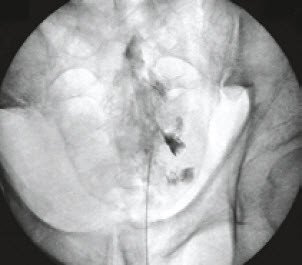

- Facettengelenkinfiltration unter Bildverstärker

- Sakralblockade (Abb.1) unter Bildverstärker und Einleitung einer Physiotherapie